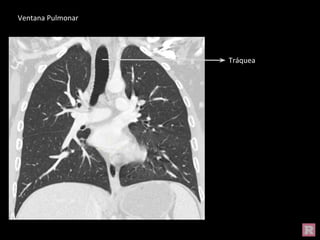

Ventana Pulmonar

Tráquea